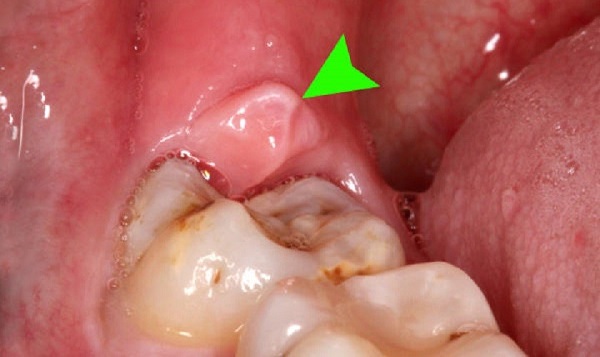

- Viêm lợi trùm: Khi răng khôn mọc, mô nướu phát triển và phủ lên một phần răng khôn đang nhú lên. Nếu răng khôn mọc thẳng, tình trạng sưng nướu răng sẽ kết thúc sau vài ngày. Tuy nhiên, nếu răng khôn mọc lệch, cơn đau này sẽ lặp đi lặp lại và việc sử dụng thuốc chỉ giúp giảm đau tạm thời.

- Sưng nướu răng khôn: Khi răng khôn mọc, sưng nướu và đau nhức xương hàm rất dễ mắc phải. Vị trí của răng khôn ở cuối hàm làm cho việc vệ sinh khó khăn, tạo điều kiện cho vi khuẩn tấn công, gây sưng mủ và viêm nhiễm.